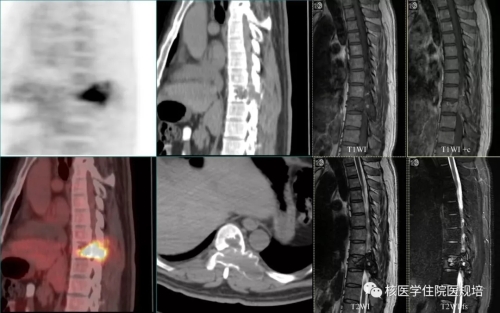

病史及检查目的: 患者63岁女性,4月余前无明显诱因出现持续性胸背部疼痛,沿肋间放射至胸部,左侧重,翻身及行走后加重,查体T4棘突压痛及叩痛(+)。行胸椎CT平扫+三维重建提示T4椎体变扁,后缘可见软组织密度影突向髓腔内,硬膜囊受压,考虑T4椎体病理性骨折可能。实验室检查:尿本周蛋白阴性;尿KAPPA轻链及LAMBDA轻链阴性;肿瘤标志物检测均为阴性。 为明确T4椎体病变性质、寻找骨转移原发灶行PET/CT检查(图2)。 图1.胸椎CT(骨窗) 图2. PET/CT图像 检查所见: T4椎体及附件区域见条状高度放射性浓聚(SUVmax:8.1),CT于相应区域可见溶骨性骨质破坏及软组织肿物影,向后累及附件并突入椎管内,椎体前缘骨皮质尚完整。左腋窝可见一FDG摄取增高淋巴结显影,考虑淋巴组织回流所致。扫描范围其余部位未见明显异常。 检查意见: T4椎体及附件骨质破坏呈葡萄糖代谢明显增高考虑恶性肿瘤可能,需鉴别原发灶不明的转移瘤、浆细胞瘤、骨巨细胞瘤、骨的嗜酸性肉芽肿及不典型淋巴瘤等,建议组织病理学检查。 手术及病理: 行胸椎椎管减压、椎弓根钉内固定术、病灶清除、椎体成形术,积水潭医院病理会诊:(胸4椎体)富含多核巨细胞病变,组织形态首先考虑骨巨细胞瘤。免疫组化:CK(-),Desmin(-),Ki67(10%-15%+),Vimentin(+),ActinSM(-),PGM-1(多核巨细胞+),KP-1(多核巨细胞+)。 病例相关知识: 骨巨细胞瘤(giant cell tumor of bone,GCT)为一种临床较为常见的骨原发性肿瘤,大部分为良性肿瘤,部分生长活跃,极少数一开始就是恶性。GCT具有丰富的血管组织并含有单核基质细胞和很多破骨细胞样的多核巨细胞,其中基质细胞决定肿瘤的性质。Jaffe等[1]首次定义GCT并根据基质细胞的异型性及有丝分裂活动进行病理分级,一般认为I级偏良性,Ⅲ级为恶性,介于两者之间的为Ⅱ级。目前WHO第四版骨与软组织肿瘤已将GCT定义为交界性肿瘤。与西方国家相比,国内GCT的发病率较高,约占所有原发骨肿瘤的20%[2]。女性发病率高于男性,多发生于青壮年,发病年龄多在20-40 岁之间,50岁以上的GCT约占9%-13%,青年人和儿童少见[3]。GCT多发生于骨骺融合后成熟的骨端[4],侵犯长骨多见,*常见于股骨下端、胫骨上端,约占50%以上,发生于非长管状骨如脊柱、骨盆、手骨、颌骨、颅骨等的GCT约占20%,但近年来也有报道GCT在脊柱的发病率增加。该病*常见的症状为肿瘤部位的疼痛与肿胀,且疼痛有活动后加重、休息后缓解的特点,手术是治疗GCT的主要方法,目前亦有一些RankL拮抗剂用于术前药物治疗。 GCT的影像表现具有一定特异性,X线平片表现为骨端偏心性、囊性、膨胀性、溶骨性骨质破坏, 无明显硬化缘,骨包壳完整或部分缺如,部分肿瘤内可见骨性分隔,呈“皂泡样”改变(图3)。CT较X线具有较高的分辨率,能更加细致入微地观察骨质破坏情况,可观察到骨质破坏区内残留的骨嵴,与X线平片上“皂泡样”改变相对应,还可以能清晰地显示破坏区内部结构及软组织肿块及周边残留的骨壳。MRI检查能够清晰显示骨巨细胞瘤的大小、位置及形态,且对肿瘤附近的水肿状况进行清晰显示,在诊断病变范围上的价值较X线与CT检查更高。在MRI检查中,肿瘤的实质部分多呈T1WI与T2WI等信号,其内常可见多发混杂信号影,提示肿瘤内部常伴有坏死、囊变和出血。 图3. 骨巨细胞瘤的皂泡样改变(左:X线片,右:99mTc-MDP骨显像)(北京大学人民医院提供) 尽管骨肿瘤的*终诊断的确立需要临床、影像、病理三结合,即“CRP诊断”,但典型的影像表现对早期临床诊疗决策的建立十分重要。18F-FDG PET/CT全身大视野成像有助于发现肿瘤累及区域,通过发现多发病灶,首先可帮助检出转移瘤或血液系统肿瘤。然而,本病例PET/CT所见为脊柱单发病变,其鉴别诊断面临更多的挑战。由于病灶呈溶骨性骨质破坏并软组织肿物形成,椎体出现病理性骨折且软组织肿物压迫硬膜囊,同时肿瘤呈FDG高摄取,鉴于患者年龄偏大,应首先怀疑恶性病变。患者无肿瘤标志物升高且PET/CT无原发肿瘤病灶显示,不支持上皮源性肿瘤脊柱转移,但从发病机率应考虑有无原发灶隐匿的可能性;病变椎体前缘保留较完整,提示肿瘤侵袭性不强,不符合侵袭性淋巴瘤或一些高度恶性肉瘤的常见表现;单发浆细胞瘤多为溶骨性且可呈膨胀性改变,破坏区可见残留的骨壳和骨嵴,但一般FDG摄取程度相对较低;骨的嗜酸性肉芽肿属于朗格汉斯组织细胞增生症虽可累及脊柱并出现病理性骨折,其FDG摄取程度亦较高,但该病多见于年轻人群。回顾性分析该患者年龄虽然不属GCT好发人群,但亦可发病,而较高的FDG摄取和较温和的骨质破坏可符合GCT表现,然而由于椎体压缩性骨折使得CT对肿瘤形态和内部结构改变的观察不满意。若能获得典型的GCT CT表现,GCT诊断应该首先考虑(图4)。 图4.典型脊柱骨巨细胞瘤的PET/CT及MRI(北京大学人民医院提供) 对于原发性骨肿瘤,18F-FDG PET/CT的摄取与肿瘤成分密切相关,富含巨细胞的肿瘤(骨巨细胞瘤、未分化肉瘤、朗格汉斯组织细胞增生症等)多可见较高FDG摄取,甚至高于常见的恶性骨原发性肿瘤(骨肉瘤、软骨肉瘤、尤文肉瘤等),而良性肿瘤或者细胞成分稀疏的恶性肿瘤FDG摄取程度较低。 小结: 本病例并非典型的骨巨细胞瘤,通过此病例提出这一临床可能遇到的情况,希望为规培的小伙伴们提供脊柱病变的鉴别诊断思路。同时强调对于骨肿瘤的诊断一定是临床、影像、病理的综合分析,对常见的骨原发肿瘤相关知识应加以了解。 作者:中日友好医院核医学科 韩萍萍 郑玉民 参考文献: [1] Jaffe Hk, Lichtenstein L, Portis RB. Giant cell tumor of bone: Its pathologic appearance, grading, supposed variants and treatment. Arch Pathol, 1940, 30: 993. [2] Szendröi M. Giant-cell tumour of bone. J Bone Joint Surg Br, 2004, 86: 5-12. [3]Murphey MD, Nomikos GC, Flemming DJ, et al. From the archives of AFIP. Imaging of giant cell tumor and giant cell reparative granuloma of bone: radiologic-pathologic correlation. Radiographics, 2001, 21: 1283-1309. [4] 段承祥,王晨光,李健丁主编. 骨肿瘤影像学. 科学出版社, 2004年第一版。